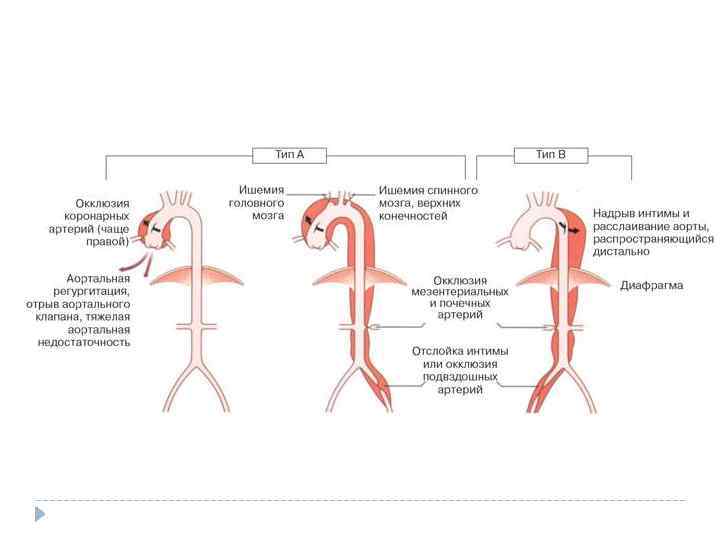

Расслаивающая аневризма аорты — разрыв аорты, который приводит к тому, что кровь затекает между слоями стенок аорты и расслаивает их дальше. Если расслоение прорывает стенку аорты полностью (все три слоя), то происходит быстрая массивная кровопотеря. В более чем 90% случаев это приводит к смерти, даже если вовремя начато правильное лечение. при надрыве интимы — боль и коллаптоидные реакции; при расслоении стенки аорты — резкая мигрирующая боль, анемизация, органные симптомы, повторные коллаптоидные реакции; при полном разрыве стенки сосуда — признаки внутреннего кровотечения и терминальный геморрагический шок.

Расслаивающая аневризма аорты — разрыв аорты, который приводит к тому, что кровь затекает между слоями стенок аорты и расслаивает их дальше. Если расслоение прорывает стенку аорты полностью (все три слоя), то происходит быстрая массивная кровопотеря. В более чем 90% случаев это приводит к смерти, даже если вовремя начато правильное лечение. при надрыве интимы — боль и коллаптоидные реакции; при расслоении стенки аорты — резкая мигрирующая боль, анемизация, органные симптомы, повторные коллаптоидные реакции; при полном разрыве стенки сосуда — признаки внутреннего кровотечения и терминальный геморрагический шок.

Систолический шум Почти у половины больных с рассливающей аневризмой аорты отмечаются признаки аортальной недостаточности - диастолический шум и снижение уровня диастолического артериального давления. Исключение ишемии по ЭКГ RG, КТ, тотальная аортография

Систолический шум Почти у половины больных с рассливающей аневризмой аорты отмечаются признаки аортальной недостаточности - диастолический шум и снижение уровня диастолического артериального давления. Исключение ишемии по ЭКГ RG, КТ, тотальная аортография